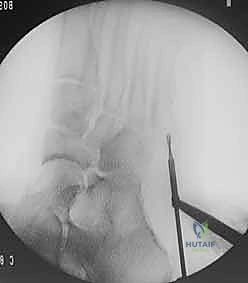

- يتم تجهيز غرفة العمليات بأحدث أجهزة التصوير الإشعاعي الفوري (C-arm) لضمان الدقة المطلقة.

- إدخال سلك التوجيه (Guide Wire): تحت توجيه الأشعة السينية المباشرة في غرفة العمليات، يتم إدخال سلك معدني رفيع جداً ليمر عبر الكسر وصولاً إلى النخاع العظمي. هذه الخطوة تتطلب دقة متناهية لضمان أن السلك في المنتصف تماماً.